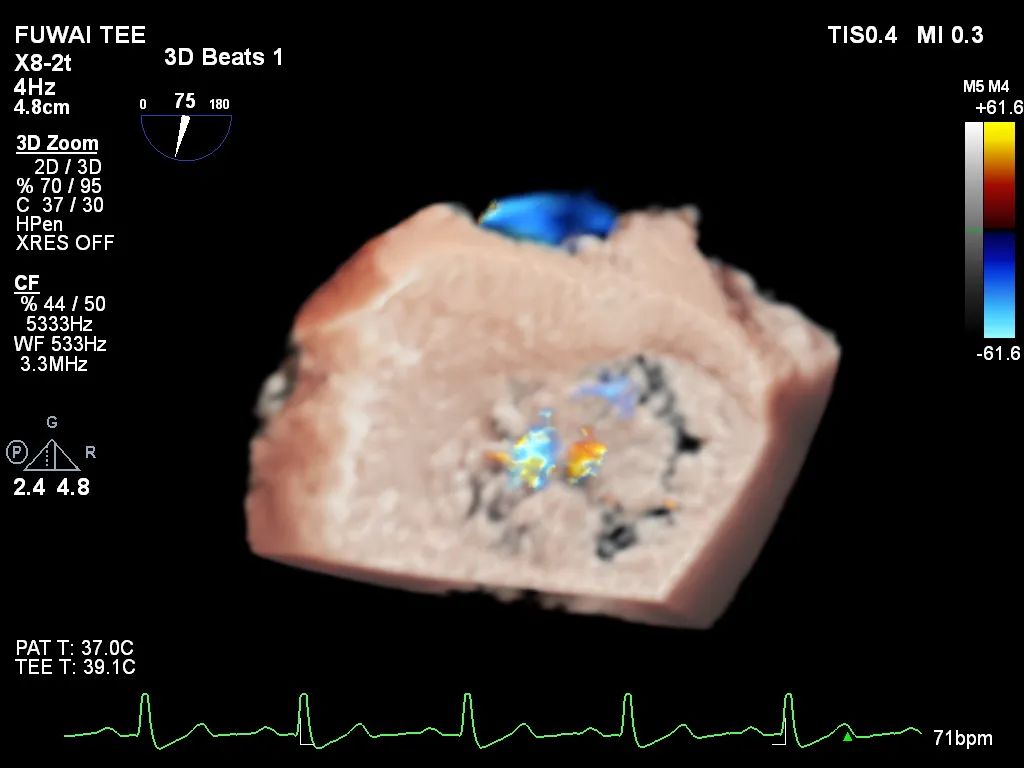

手术团队使用MitraClip®独特的三层双调弯导管,经股静脉穿刺,在食道超声引导下完成房间隔穿刺。穿刺后将导管送入左心房,对准二尖瓣目标位置P2区域。准确捕捉瓣叶,二尖瓣夹释放后,超声显示反流几近消失,患者各项生理指标正常,手术顺利完成。